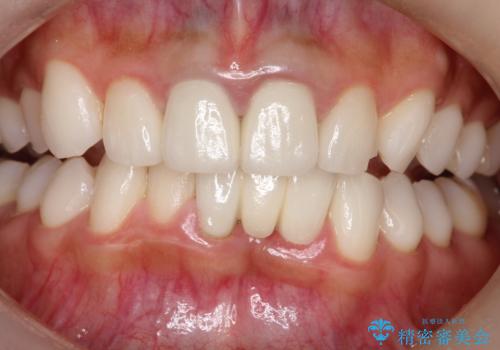

[エアフロー] スプレーの噴射によりしつこい色素沈着やプラークを除去

![[エアフロー] スプレーの噴射によりしつこい色素沈着やプラークを除去の症例 治療前](https://seimitsushinbi.jp/wp/wp-content/uploads/2021/11/IMG_9998-500x350.jpg?v=1636593297)